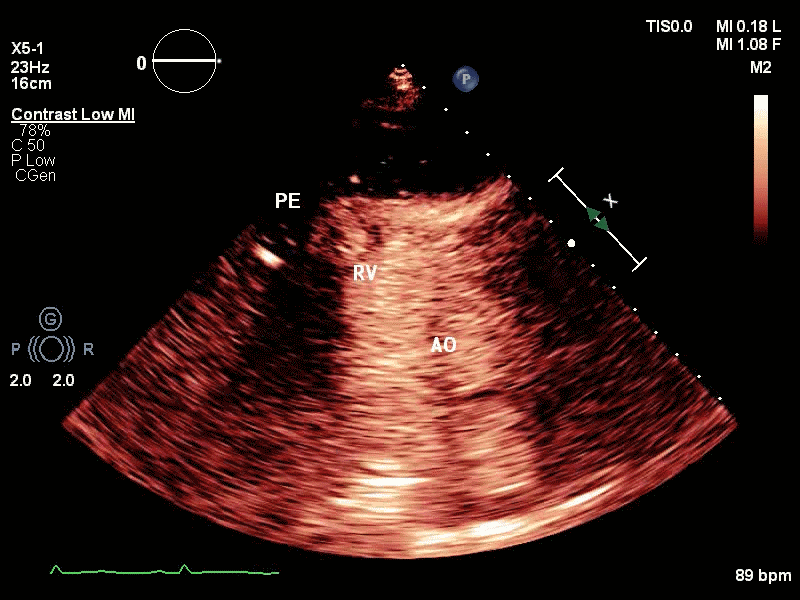

视频2 -3 : Contrast-Low MI模式下,心包腔内亦可见少量的造影剂回声。

视频5-6 :心脏超声造影提示:右室流出道与左室心尖间外壁血肿形成。中大量心包积液。

虽然患者的临床表现符合心包压塞,且超声心动图发现的中大量心包积液可以帮助肯定心包压塞的存在,且二维超声心动图观察到了可疑为血肿的低回声区,甚至用彩色多普勒就可以观察到心包腔内暗淡的红蓝色血流信号,但由于彩色多普勒的伪像多,彩色溢出现象常见,故为了进一步明确心包压塞的病因,选择进行心脏超声造影。